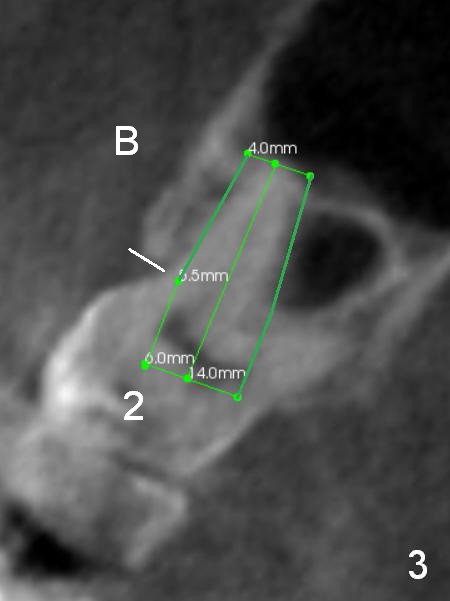

When the immediate implant is placed in the buccal socket (Fig.3 CT coronal section of the tooth #2), the implant appears to be shallow with possibility of thread exposure (white line: buccal (B) crest and beginning of the threads) unless the implant is pushed into the sinus.